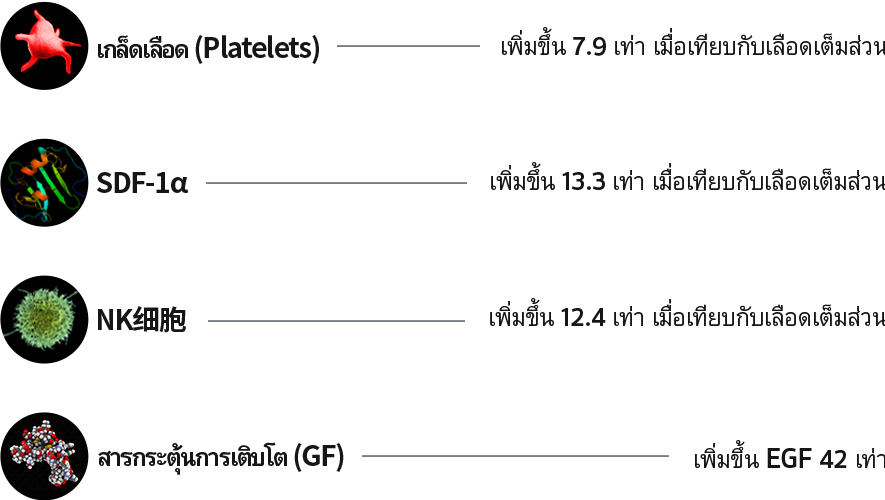

ประกอบไปด้วยคอลลาเจน 70%

ผิวกระชับเปล่งปลั่งทั่วร่างกายด้วยคอลลาเจน ถึง70%

คอลลาเจน เป็นเส้นใยโปรตีนที่เป็นส่วนประกอบของผิวหนัง ช่วยยึดเกาะ

เพิ่มความยืดหยุ่นและความชุ่มชื้นแก่ผิว โดยปกติร่างกายจะสามารถผลิตคอลลาเจนได้เอง

แต่เมื่ออายุมากขึ้น ร่างกายจะสามารถสร้างคอลลาเจนได้น้อยลง

ซึ่งทำให้ผิวหนังหย่อนคล้อยและเกิดริ้วรอยตามวัยได้